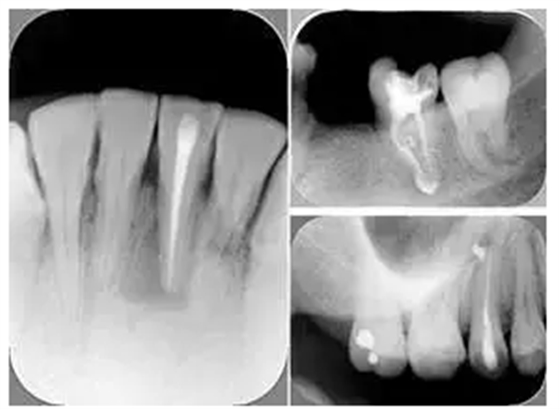

2. X 線片

共有 4 張 X 線片,分別是術(shù)前、診斷絲 、主牙膠尖確認(rèn)、術(shù)后。

( 1 )術(shù)前:術(shù)前 X 線片用來了解牙齒的大概情況。術(shù)前預(yù)期為多根牙時(shí) X 線片應(yīng)偏頭拍攝。

( 2 )診斷絲:根據(jù)術(shù)前 X 線片進(jìn)行開髓、根管的初步預(yù)備后,需要插入診斷絲,用來指示工作器械位置。常用 10 號(hào)或 15 號(hào)擴(kuò)大器作為診斷絲插入牙髓腔。

( 3 )主牙膠尖確認(rèn):通過術(shù)前預(yù)期和診斷絲診斷,明確工作長(zhǎng)度、牙根走向,進(jìn)行根管預(yù)備。之后應(yīng)進(jìn)行主牙膠尖(中銼)確認(rèn),已明確根管是否適合充填。

( 4 )術(shù)后:觀察治療效果。

左圖為根管充填術(shù)后 X 線片。圖中可見,根管充填較好。右下圖有白色小點(diǎn),為側(cè)方加壓導(dǎo)致糊劑擠出所致,表明根管充填比較致密。

致密、恰到好處的充填可去除干凈根管里感染灶,機(jī)體逐漸恢復(fù)。

多根牙時(shí)候需進(jìn)行偏移投照,正位投照無法說明具體哪根牙根管充填效果。 二、根管預(yù)備及充填要求